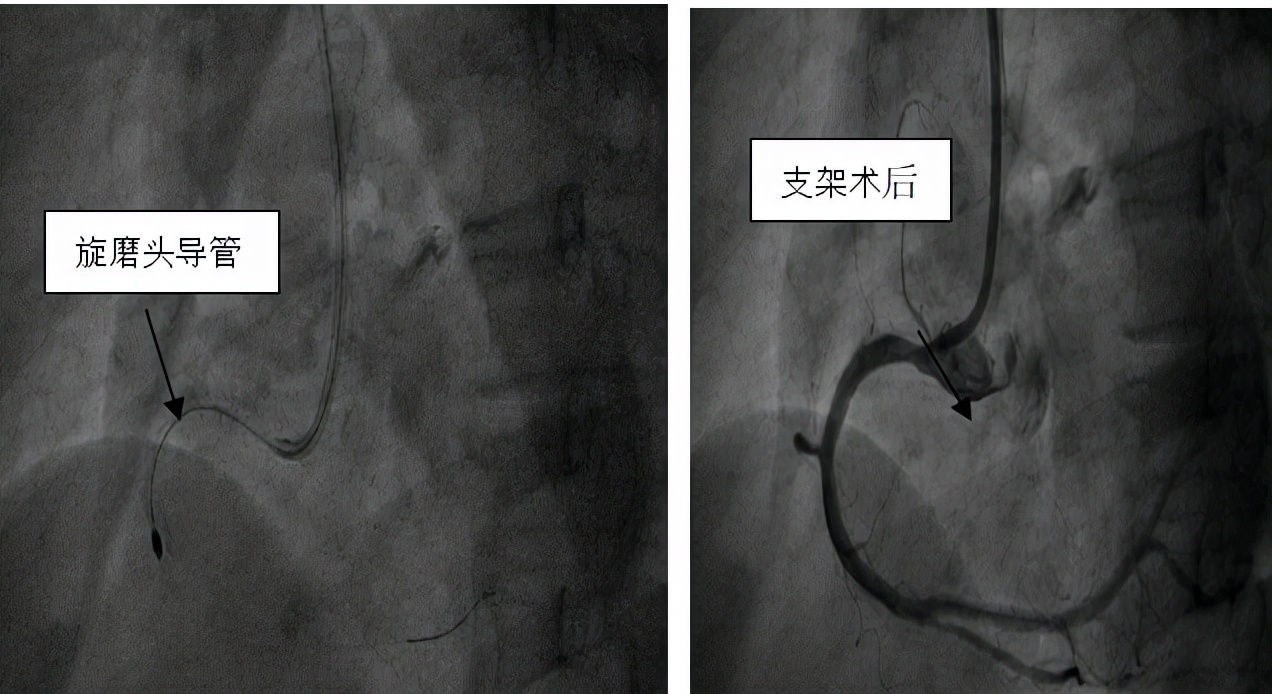

3月4日,辽阳市中心医院心血管五病房成功完成2例冠状动脉旋磨术,为严重血管钙化患者顺利植入支架。

患者主因"阵发性胸闷"就诊中心医院心血管五病房,诊断为不稳定型心绞痛。冠脉造影显示患者冠状动脉狭窄分别为90%、85%,伴钙化严重。严重的血管钙化使冠脉支架通过困难及支架膨胀不良等情况。

那么钙化严重的血管能不能做支架?赵丽君主任带领的冠脉介入团队,深知对冠状动脉钙化患者行PCI手术是介入治疗的难题之一,成功率低。但患者的病情又亟需实施介入治疗。为此,赵丽君主任仔细分析病情,制定手术策略,对钙化的病变血管做好支架植入治疗前的预处理工作,为钙化的血管行冠状动脉旋磨术,通过差异性切割原理,将钙化病变打磨,最终顺利植入支架,解决了严重钙化病变支架植入的治疗难题。